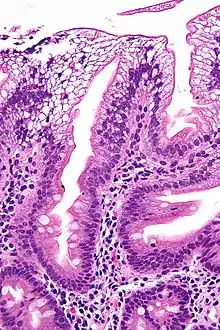

There is an absence of apolipoprotein B. On intestinal biopsy, vacuoles containing lipids are seen in enterocytes. This disorder may also result in fat accumulation in the liver (hepatic steatosis). Because the epithelial cells of the bowel lack the ability to place fats into chylomicrons, lipids accumulate at the surface of the cell, crowding the functions that are necessary for proper absorption.

Micrograph showing enterocytes with a clear cytoplasm (due to lipid accumulation) characteristic of abetalipoproteinemia. Duodenal biopsy. H&E stain.

Duodenal biopsy from ABL individual shows vacuolated enterocytes